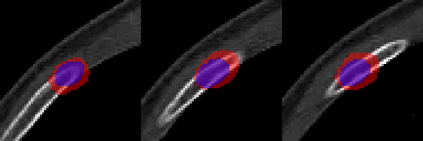

Rib fractures are a common and potentially severe injury that can be challenging and labor-intensive to detect in CT scans. While there have been efforts to address this field, the lack of large-scale annotated datasets and evaluation benchmarks has hindered the development and validation of deep learning algorithms. To address this issue, the RibFrac Challenge was introduced, providing a benchmark dataset of over 5,000 rib fractures from 660 CT scans, with voxel-level instance mask annotations and diagnosis labels for four clinical categories (buckle, nondisplaced, displaced, or segmental). The challenge includes two tracks: a detection (instance segmentation) track evaluated by an FROC-style metric and a classification track evaluated by an F1-style metric. During the MICCAI 2020 challenge period, 243 results were evaluated, and seven teams were invited to participate in the challenge summary. The analysis revealed that several top rib fracture detection solutions achieved performance comparable or even better than human experts. Nevertheless, the current rib fracture classification solutions are hardly clinically applicable, which can be an interesting area in the future. As an active benchmark and research resource, the data and online evaluation of the RibFrac Challenge are available at the challenge website. As an independent contribution, we have also extended our previous internal baseline by incorporating recent advancements in large-scale pretrained networks and point-based rib segmentation techniques. The resulting FracNet+ demonstrates competitive performance in rib fracture detection, which lays a foundation for further research and development in AI-assisted rib fracture detection and diagnosis.